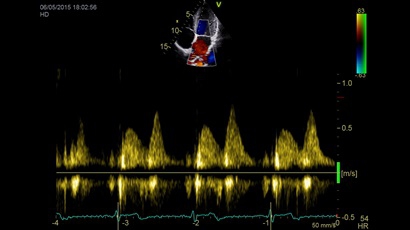

Тканевой допплер:

Да

TDI:

• Режимы: 4D, 2D (B-режим), цветной допплеровский режим, режим энергетического допплера, M-режим, цветной M-режим, спектральные режимы импульсно-волнового допплера (PW) и непрерывно-волнового допплера (CW), визуализация скорости движения тканей.

• Q-ANALYSIS - опция количественного анализаданных тканевого допплера, контрастных исселедований.